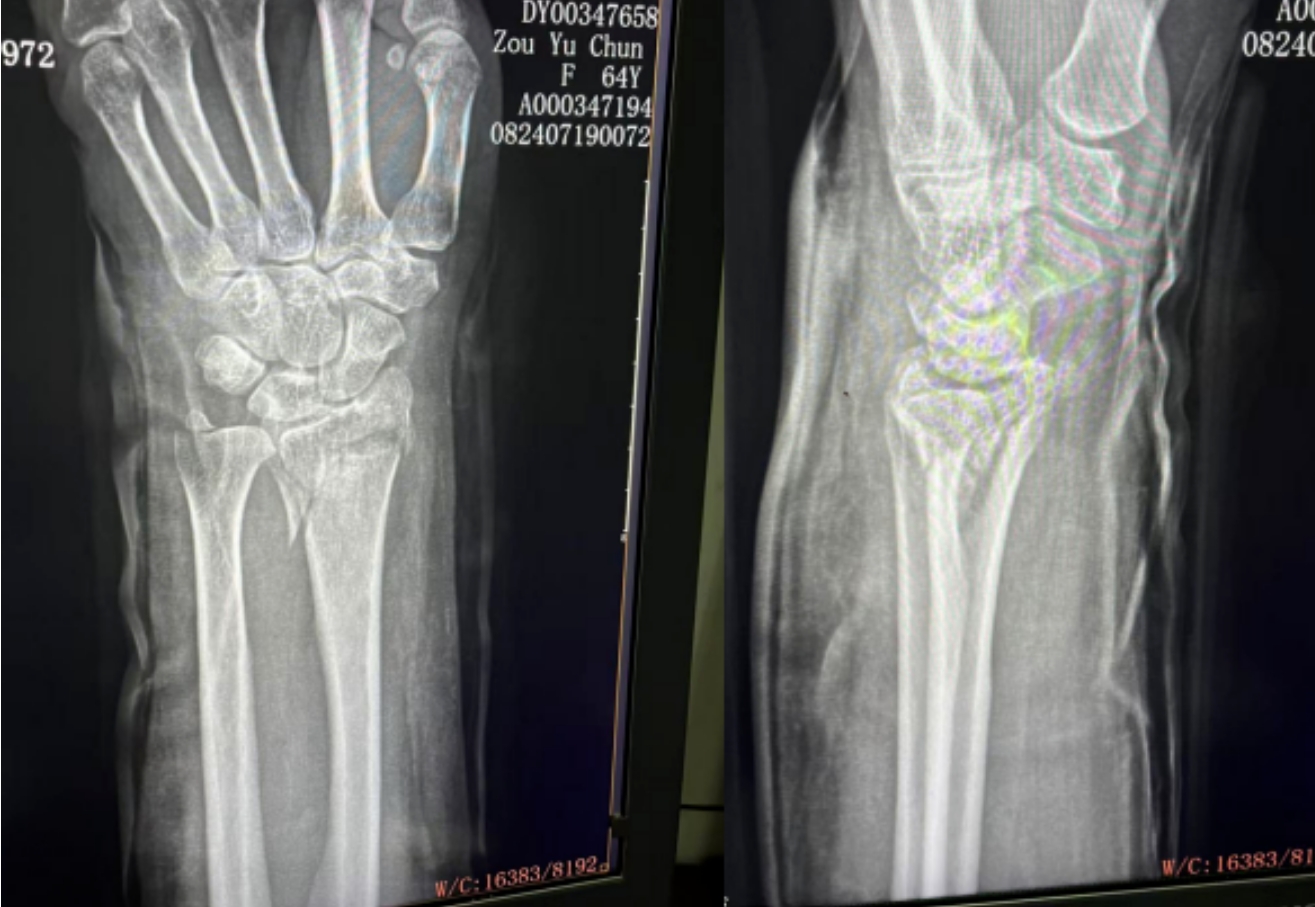

橈骨遠(yuǎn)端骨折復(fù)位前 橈骨遠(yuǎn)端骨折復(fù)位后